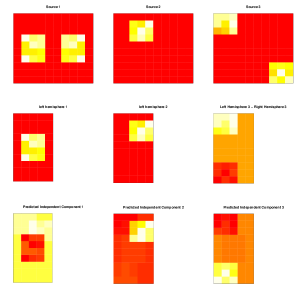

The following simple example is given to initially demonstrate the effectiveness of H-gICA. Suppose the number of subject is and the number of underlying sources is . For each subject , the data matrix is from the model with and . We further assume that

As shown in Figure 1, three different source matrices () are generated: one is symmetric; another is only in one hemisphere; and the third has two asymmetric blocks of activated voxels.

These results are shown in the bottom row of Figure 1, highlighted by H-gICA’s separation of the three source matrices and its meaningful prediction for all of them.